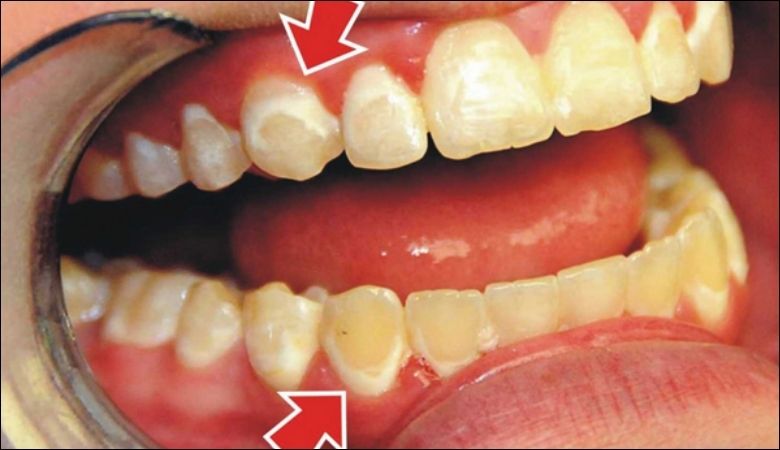

Triệu chứng viêm nha chu cần nhận biết

Triệu chứng viêm nha chu bao gồm nướu sưng đỏ, dễ chảy máu khi chải răng hoặc ăn nhai. Hơi thở có mùi hôi kéo dài và răng lung lay là dấu hiệu bệnh đã tiến triển nghiêm trọng.

Người bệnh có thể cảm thấy đau nhức ở nướu hoặc nhận thấy nướu tụt, làm lộ chân răng. Nha khoa Parkway khuyến khích thăm khám ngay khi nhận thấy các triệu chứng viêm nha chu để được điều trị kịp thời.